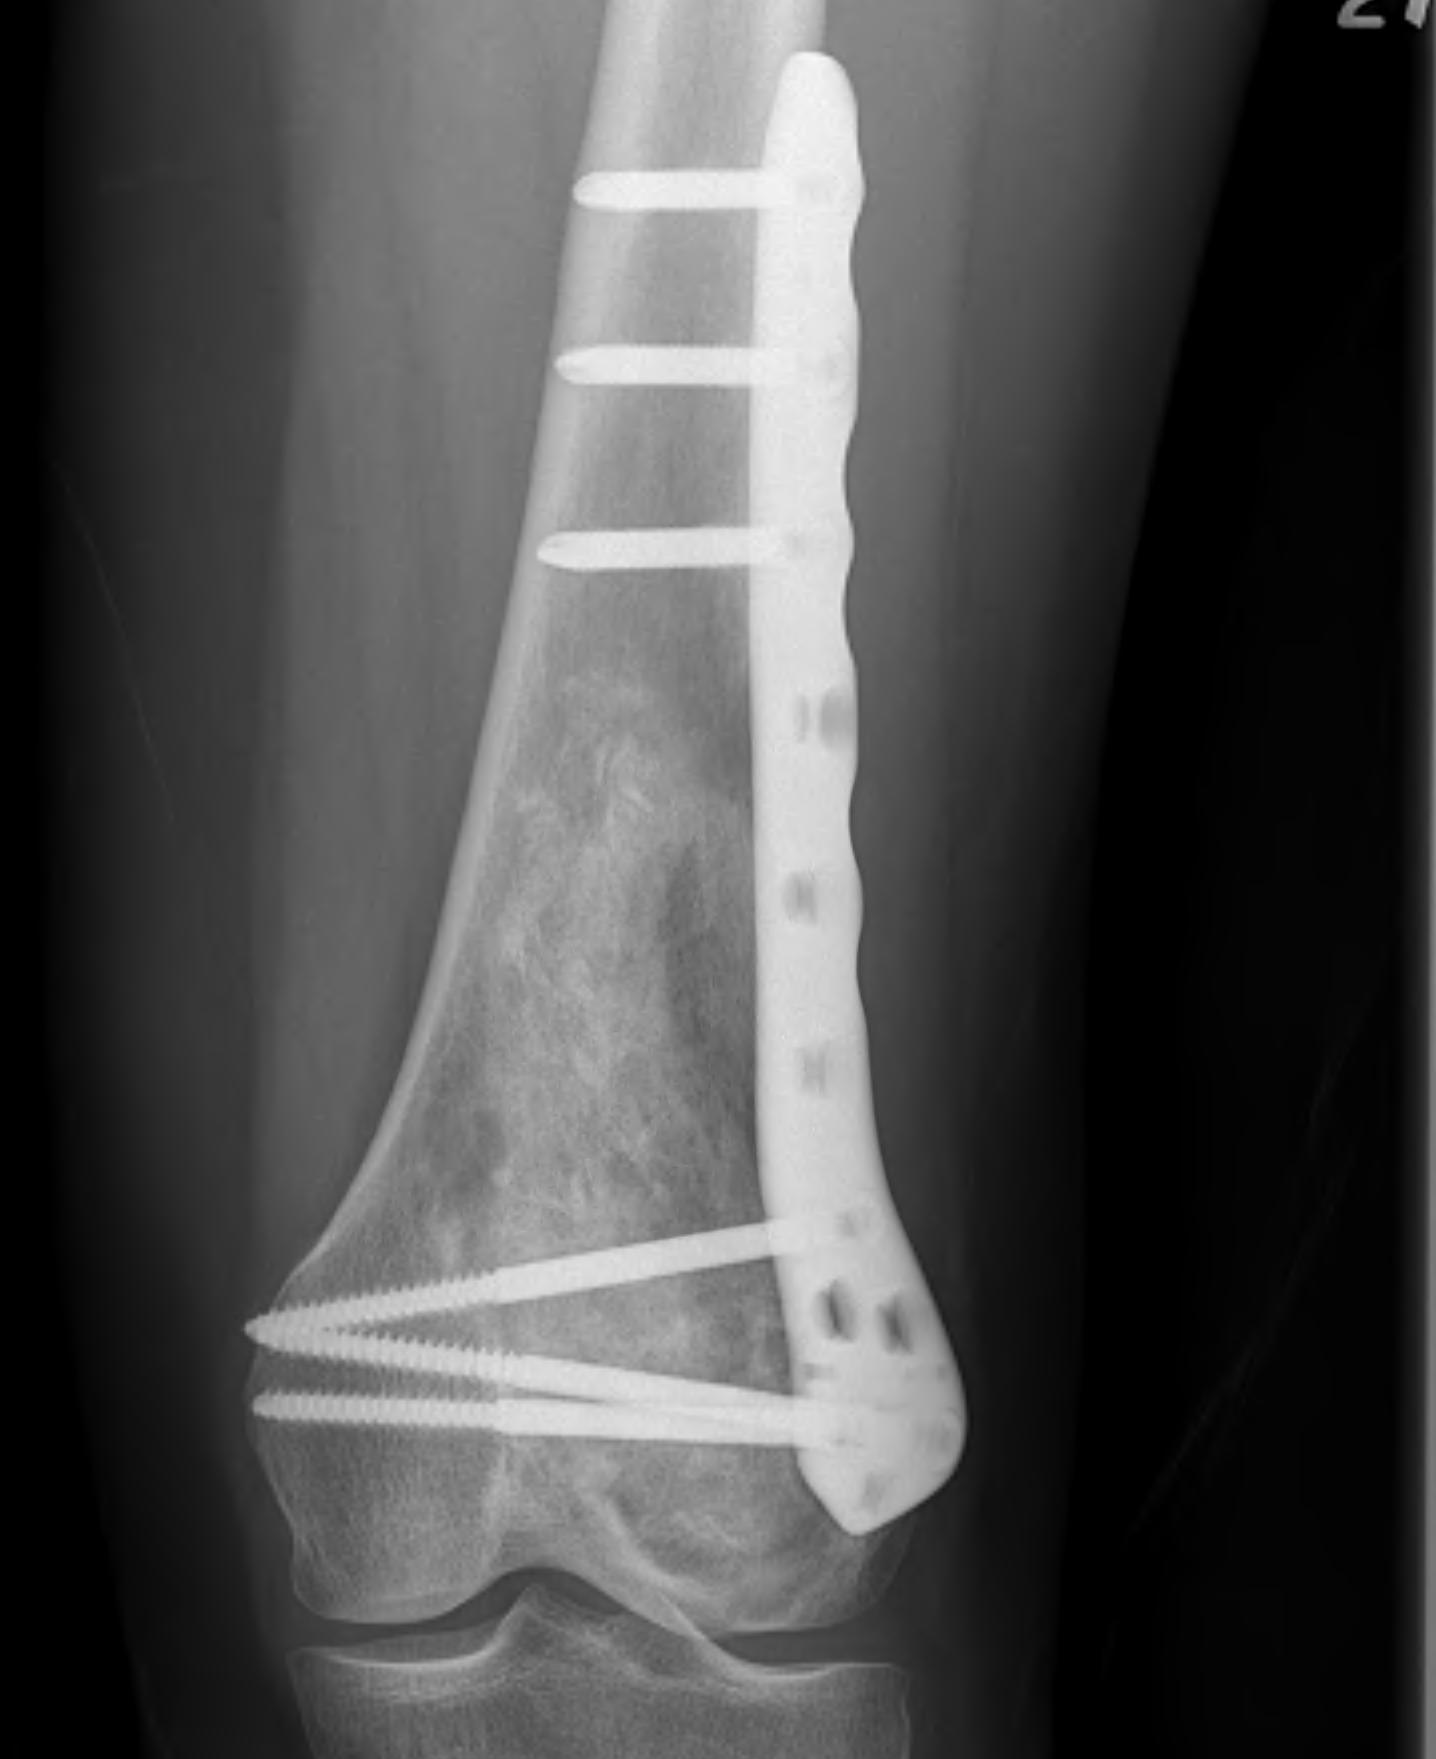

Weight bearing joints

Options

Currettage and bone graft

Currettage / bone graft / fixation